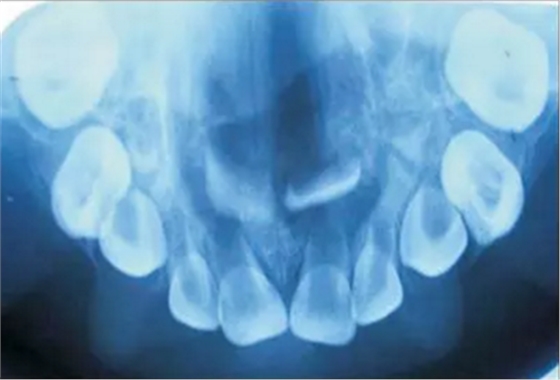

患者為18個(gè)月齡的幼兒,主訴為口腔上腭大面積潰瘍伴鼻腔反流及口腔異味。患兒1個(gè)月前曾在外院治療過肺炎,治療過后一個(gè)月,患兒家長發(fā)現(xiàn)患兒上腭出現(xiàn)一小潰瘍并再一次就診。潰瘍?cè)谌靸?nèi)顯著增大并導(dǎo)致上腭穿孔。患兒出現(xiàn)吞咽困難及鼻腔反流等癥狀。為求治療穿孔及相關(guān)癥狀及預(yù)防吸入性肺炎來我院就診?;純簺]有糖尿病、惡性血液病等病史,也沒有鼻竇炎或流涕等癥狀??趦?nèi)檢查發(fā)現(xiàn)上腭一暴露骨面的巨大潰瘍,范圍從腭中縫至軟腭,局部穿孔?;純嚎诘?、舌、頰粘膜、唇、鼻中隔皆正常,上頜乳切牙、乳側(cè)切牙、左下頜第一乳磨牙已萌出。

口內(nèi)咬合片可見上頜3×4cm大小低密度影,上頜中切牙恒牙胚移位。

初步診斷為口腔毛霉菌病。取部分軟腭組織做病理學(xué)檢查。病理檢查顯示組織中含有大量無包膜的真菌、壞死血管組織,結(jié)果支持毛霉菌病的診斷。